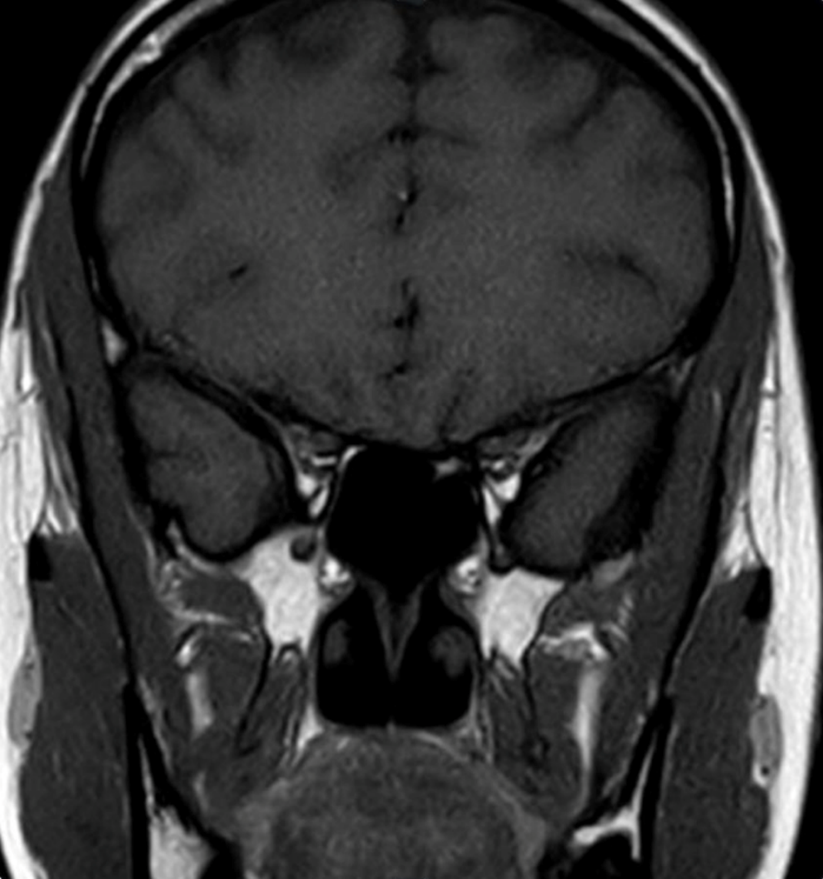

A low-dose 1-mg overnight dexamethasone suppression test produced an elevated serum cortisol of 991.03 nmol/L, showing unsuppressed morning cortisol, with an ACTH level of 577 pg/mL (reference, 7.2–63.3 pg/mL). Because of the markedly elevated ACTH, magnetic resonance imaging of the brain was performed to evaluate for a pituitary source but was negative (Figure 1). Cortisol levels remained elevated at >1750 nmol/L after the 8-mg high-dose dexamethasone suppression test, suggestive of an ectopic source.

Figure 1. Coronal view of a brain magnetic resonance imaging with contrast showing normal pituitary gland.